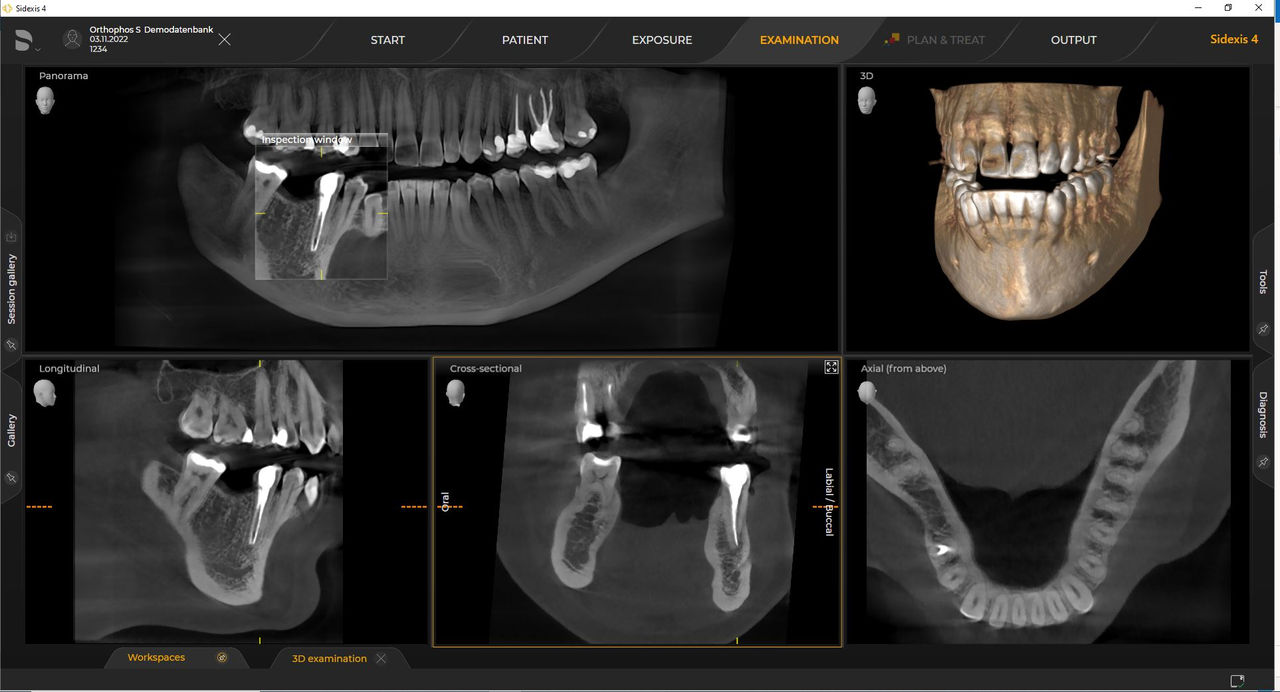

Las unidades de radiología de Dentsply Sirona funcionan exclusivamente con Sidexis 4. Sin embargo, la migración de datos de Sidexis XG a Sidexis 4 es muy fácil. Sidexis 4 permite una experiencia digital completa con las últimas herramientas